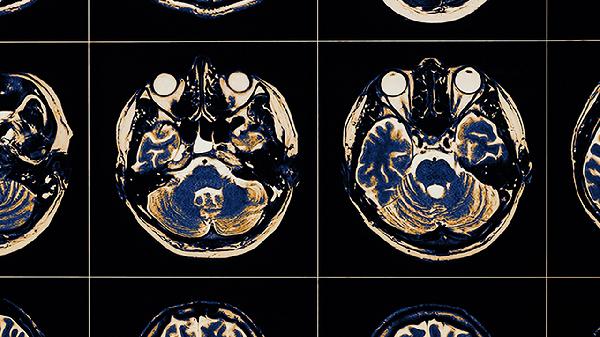

功能性核磁共振研究证实,长期遭受语言攻击的儿童大脑灰质体积减少,特别是前扣带回和颞上回等区域。这些结构与共情能力、语言理解密切相关,结构异常可能导致社交认知障碍,部分儿童成年后仍保留异常的脑功能连接模式。